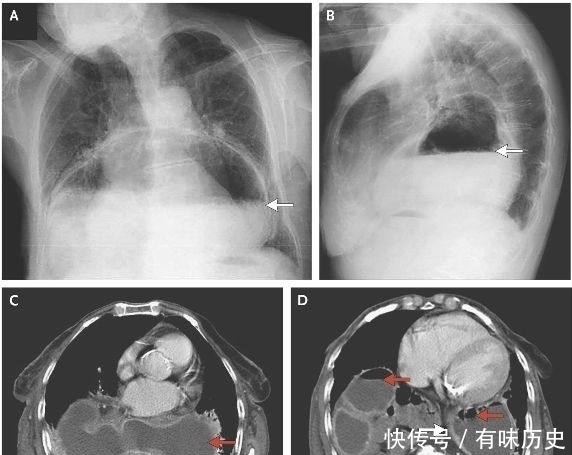

食管裂孔疝指的是人体内脏器官(主要是胃)通过膈食管裂空进入人体的胸腔所引发的疾病。在膈疝中这种病症最为常见,属于消化内科疾病,食管裂孔疝的病发不分年龄,可以是任何人群。病发原因也不是一种,有些人是先天性的食管发育不足,还有的是因为肌肉萎缩又或者是后天的腹腔压力过大导致以及受到创伤等。

食管裂孔疝有不同的临床表现。首先是胃食管反流症状,即胸骨后或者剑突下有烧灼感、胃内容物上反感、上腹疼痛感等。并且疼痛感还可能放射到背部、肩部以及颈部等身体部位。其次是并发症,其中包括裂孔疝的出血现象,严重的可致贫血,并且疝入的胃和肠如果发生溃疡会造成呕血和黑便的现象,还有吞咽食物困难、疼痛以及呕吐现象。除上述以外,裂孔疝病人如果突然感觉上腹有剧烈的疼痛感并伴随呕吐,完全不能吞咽或者出现大出血情况,则提示发生急性嵌顿。